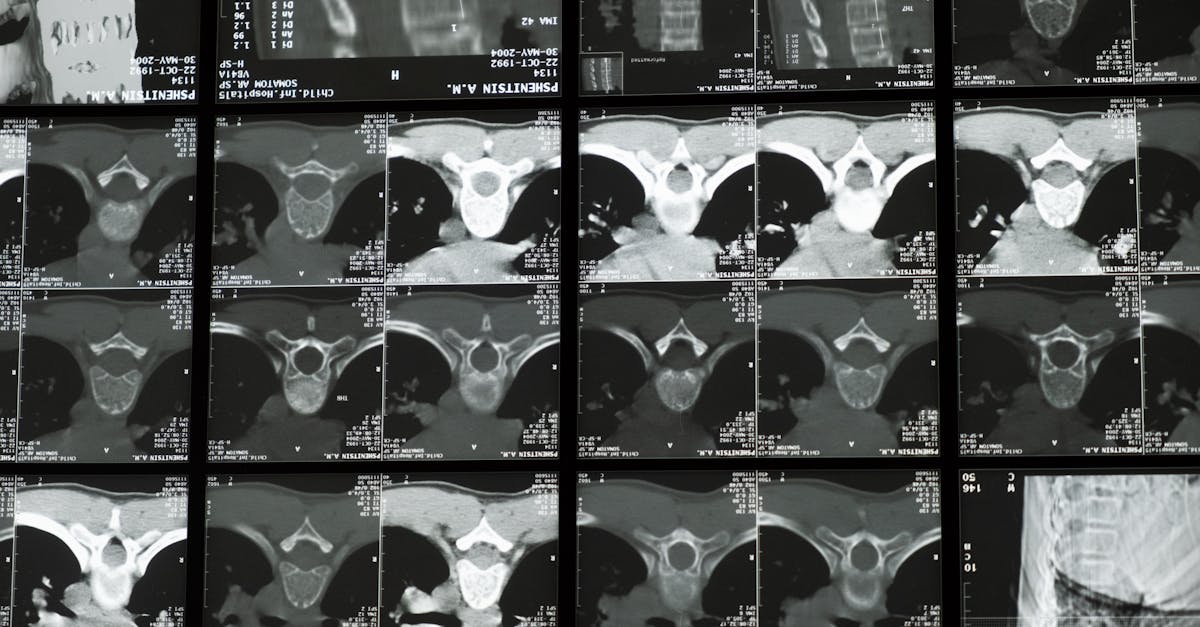

La décompression neurovertébrale utilise un équipement spécialisé qui applique une traction douce sur la colonne vertébrale. Ce processus crée un espace entre les vertèbres, ce qui réduit la pression exercée sur les disques et les nerfs. Les patients souffrant de douleurs aiguës, telles que les hernies discales ou la sténose spinale, peuvent bénéficier de ce traitement. La technique favorise également une meilleure circulation sanguine dans la région affectée, ce qui contribue à la guérison des tissus endommagés.

La décompression neurovertébrale est une méthode innovante et non invasive, idéale pour les patients souffrant de douleurs chroniques liées à la colonne vertébrale et qui hésitent face à des interventions chirurgicales. En appliquant une traction douce sur la colonne vertébrale, cette technique vise à réduire la pression sur les disques intervertébraux et les nerfs, favorisant ainsi une circulation sanguine améliorée et une régénération des tissus. Dans cet article, nous explorerons les avantages de cette méthode pour les patients, les indications appropriées, ainsi que le processus de traitement.

Le traitement se déroule généralement sur une série de séances, durant lesquelles le patient est installé confortablement sur une table spécialisée. Le praticien applique une traction douce et contrôlée sur la colonne vertébrale, permettant ainsi de créer un espace entre les vertèbres. Ce processus favorise la réduction immédiate de la douleur et construit un environnement favorable à la guérison.

La technologie utilisée dans la décompression neurovertébrale repose sur un principe simple et efficace : créer un espace entre les vertèbres. Cette méthode utilise un équipement spécialisé qui applique une traction douce et contrôlée sur la colonne vertébrale. En créant cet espace, la pression sur les disques intervertébraux et les nerfs est considérablement réduite, ce qui permet d’atténuer les douleurs et d’améliorer la circulation sanguine dans la région affectée. La décompression favorise également une meilleure régénération des tissus, contribuant ainsi à un processus de guérison optimal.